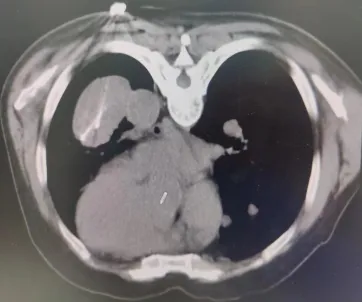

近期,我院肿瘤科裴志东主任团队为一例甲状腺癌肺转移患者成功实施了肺部病灶电冷消融术,这是我院开展的首例电冷复合消融术,手术持续120分钟,操作过程安全可控,术中术后生命体征平稳。

患者病灶位于左下肺,大小8.5*5.6cm,患者俯卧位CT扫描定位,左下肺可见肿块影,局部麻醉后,按照手术设计穿刺路径,分别将阳极针、阴极针经皮穿刺进入病灶,通过冷消融4个循环、电解消融1个循环后,CT扫描可见肺内病灶坏死明显,手术2小时后顺利结束。术后病人无不适症状,3天后好转出院。